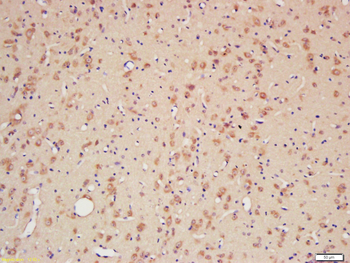

Anti-Cyclophilin A/PPIA Antibody [orb19174]

FC, ICC, IF, IHC, IHC-Fr, WB

Human, Mouse, Rat

Rabbit

Polyclonal

Unconjugated

10 μg, 100 μgCYPA Rabbit Polyclonal Antibody [orb100498]

FC, IF, IHC-Fr, IHC-P, WB

Bovine, Canine, Porcine, Rabbit

Human, Mouse, Rat

Rabbit

Polyclonal

Unconjugated